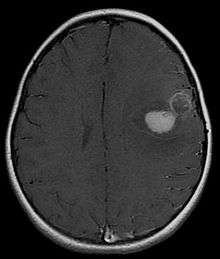

Primitive neuroectodermal tumor (PNET) is a malignant (cancerous) neural crest tumor.[1] It is a rare tumor, usually occurring in children and young adults under 25 years of age. The overall 5 year survival rate is about 53%.[2]

It is classified into two types, based on location in the body: peripheral PNET and CNS PNET.

PNET of the CNS

PNET of the CNS generally refer to supratentorial PNETs.